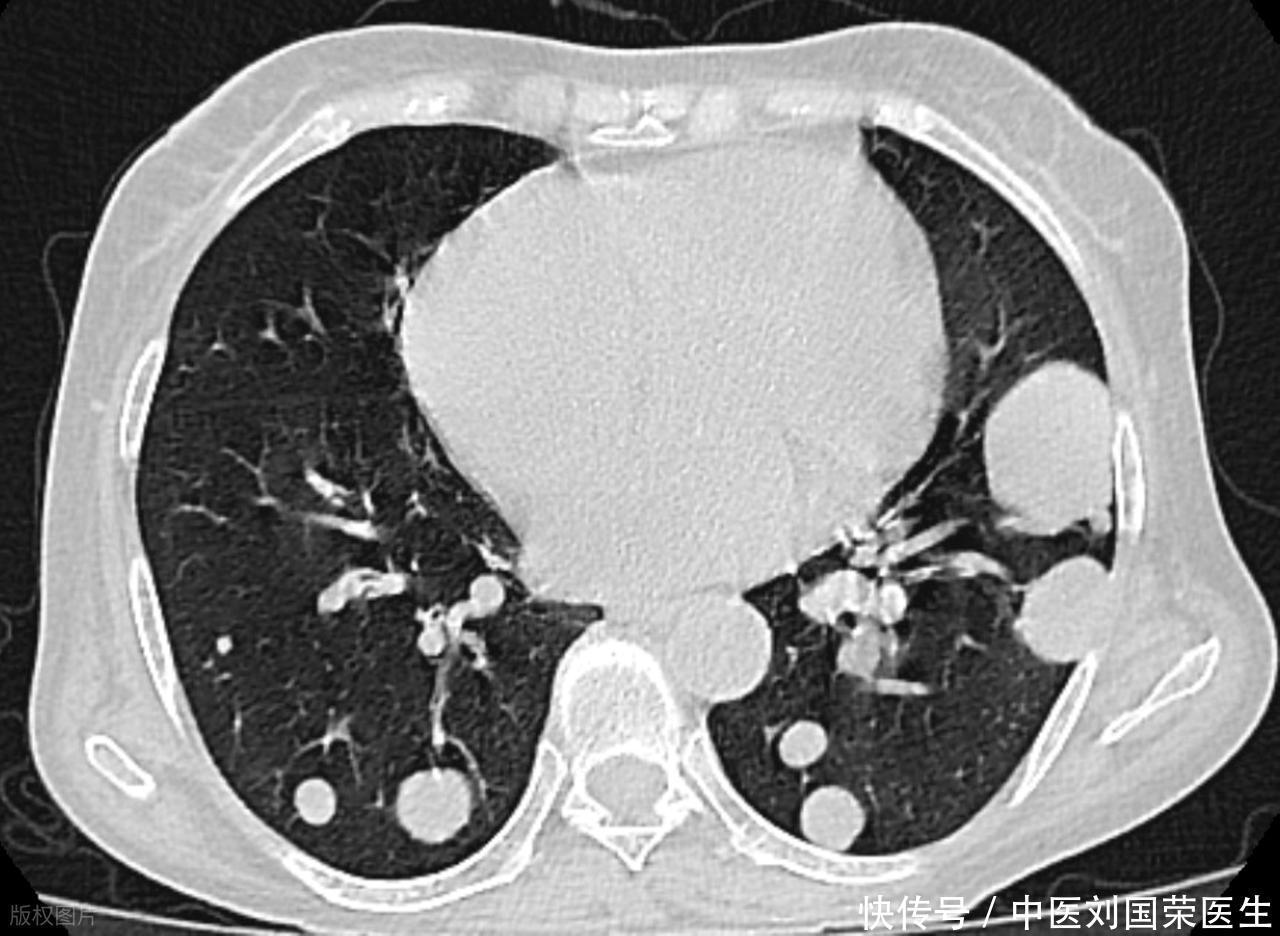

“结节”是一种影像学描述,像在肺里按下一个小小“书签”:尺寸多在毫米级,来源可能是陈旧炎症、瘢痕、灰尘沉着,甚至一次感冒后的修复痕迹。它们常年不变或缓慢淡出,这类“安静结节”无需过度解读。真正拉高风险感受的,是报告里出现某些“字眼”:毛刺提示边缘像小刺不够圆顺,分叶说明轮廓起伏像被掐过的叶片,胸膜牵拉意味着周边组织被轻微拉扯,血管集束像几束小血管朝结节汇拢,实性成分较多时密度更高、可疑度更上一个台阶,短期增大则是时间轴上的红灯。这些词并不等同“恶”,却会把结节放进更严密的随访与评估路径里:医生会结合大小、密度、形态、所在肺段以及你的吸烟史、家族史,来判断“观察—复查—进一步检查”的顺序,而不是一看到结节就谈“切”。

影像随访像给时间加刻度。对稳定、边界清楚、体积小的“安静结节”,复查间隔可相对拉长;若合并上面提到的高警觉词语,或位于高风险人群(如长期吸烟、既往肿瘤史),复查就会更密:先看短期是否“长相变了”,再看半年到一年的趋势是否“性格变了”。CT不必层层叠加成“影像焦虑”,关键是用同一设备、相近参数对比,避免因拍摄差异造成“假增大”。当医生建议进一步行薄层CT、定位扫描或功能评估时,这并非“坏结果宣布”,而是为了把模糊的影像语言翻译得更清楚。